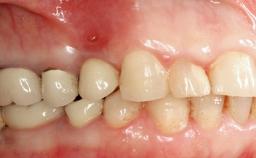

A 35-year old female patient was referred to the Department of Oral Surgery and Stomatology at the University of Bern, Switzerland, for examination of an implant site that had exhibited clinical signs of slightly delayed wound healing. In addition, the referring clinician found no evidence for a facial bone wall when she raised a flap to gain access to the implant for abutment connection. Four months earlier, she had inserted a bone-level implant in a single-tooth gap, where the lateral incisor had been extracted due to a chronic periapical lesion on the mesial aspect of the root. Implant placement was combined with simultaneous bone augmentation using deproteinized bovine bone mineral (DBBM, Bio-Oss®; Geistlich, Wolhusen, Switzerland) and a collagen membrane (Bio- Gide®; Geistlich), followed by primary wound closure. The patient also provided the postsurgical radiograph that displayed the implant with a 3.5-mm healing cap.

Case Type Single-Tooth Space

Jaw Maxilla

Area Anterior